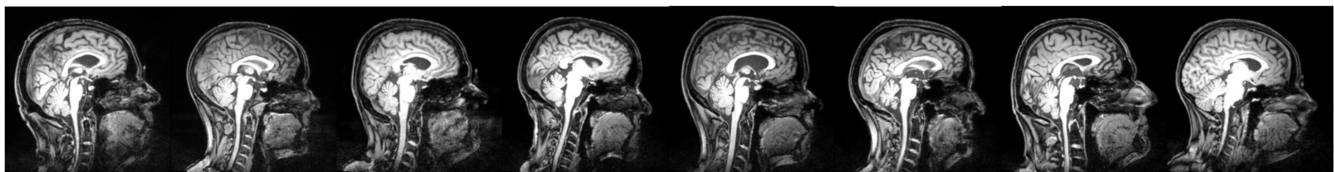

Good luck following the arrows

Describes the usual preprocessing steps:

A mean image is calculated during realignment. The mean image is then coregistered to the structural scan, which is normalized to a standard brain. The normalization parameters are then used on the functional scans to normalized everything.